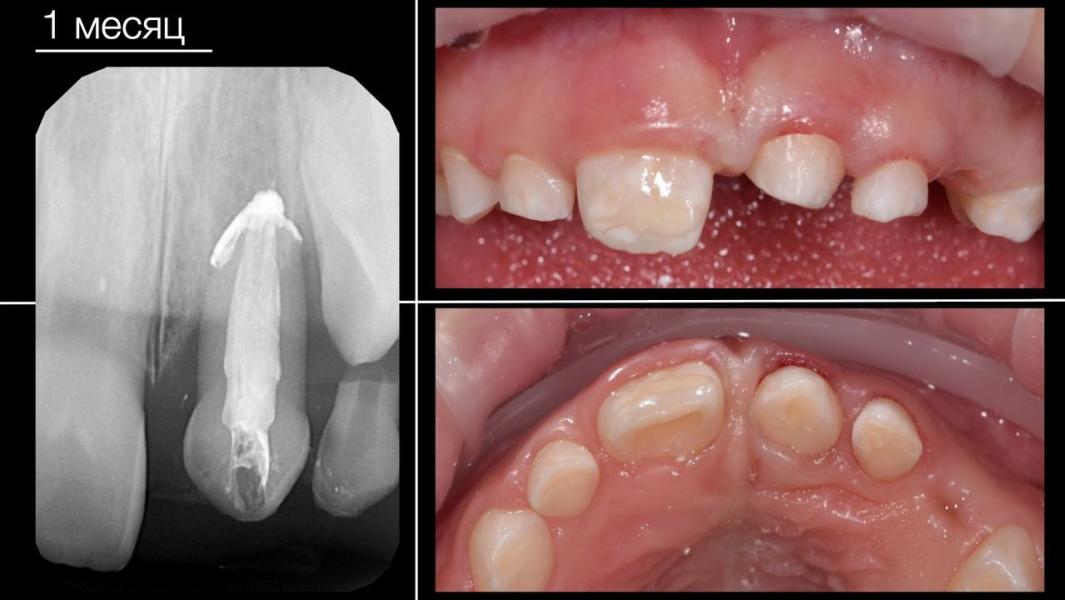

✔В нашем случае донором стал молочный клык, которые мы "забрали" раньше чем он бы выпал естественным путем.

🔹срок реабилитации меньше - полноценно жевать зубом можно уже через месяц.

А в этой работе была команда 5 :

Хирургия: Новомирский Р.А.

Эндодонтия: Тимошенко О.А.

Реставрация: Тишкина О.С.